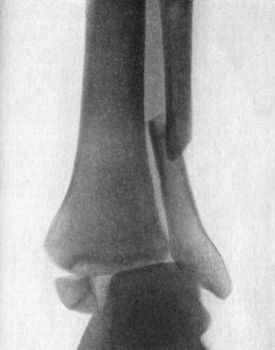

Fig. 3.—Showing (1) Oblique fracture of Tibia; (2)

Oblique fracture with partial separation of Epiphysis of upper end of

Fibula; (3) Incomplete fracture of Fibula in upper third. Result of

railway accident. Boy æt. 16.

(2) According to the Direction of the Break.—Transverse fractures are those in which the bone gives way more or less exactly at right angles to its long axis. These usually result from direct violence or from end-to-end pressure. Longitudinal fractures extending the greater part of the length of a long bone are exceedingly rare. Oblique fractures are common, and result usually from indirect violence, bending, or torsion (Fig. 3). Spiral fractures result from forcible torsion of a long bone, and are met with most frequently in the tibia, femur, and humerus.